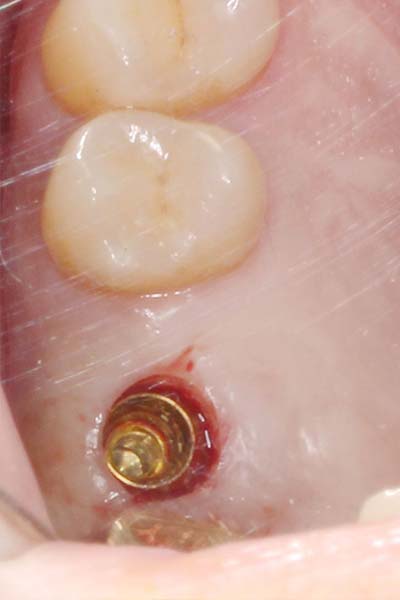

微創植牙 首頁 案例分享 人工植牙 微創植牙 微創植牙 牙周病的牙齒,因為骨頭破壞,只好拔除 拔牙後,置入骨粉,靜待骨頭癒合 晴美牙醫擁有豐富竹北微創植牙經驗,欲瞭解更多相關知識,可至診療項目-微創植牙頁面。 傷口癒合良好 微創不翻瓣 置入植牙 裝置假牙